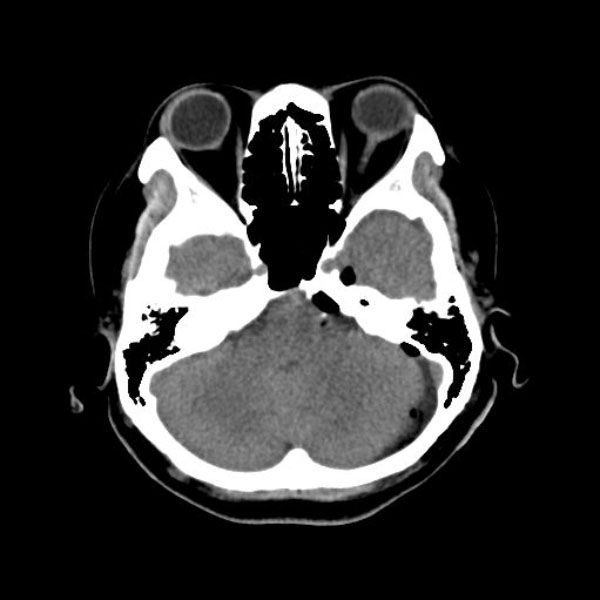

症例 '26年3月

No.

585

手術医師

手術年月

年齢

病名

術式

手術前

減圧前

減圧後

手術後

大阪府の病院

'26年3月

40代

左顔面痙攣

(痙攣をとること)

術後血管撮影